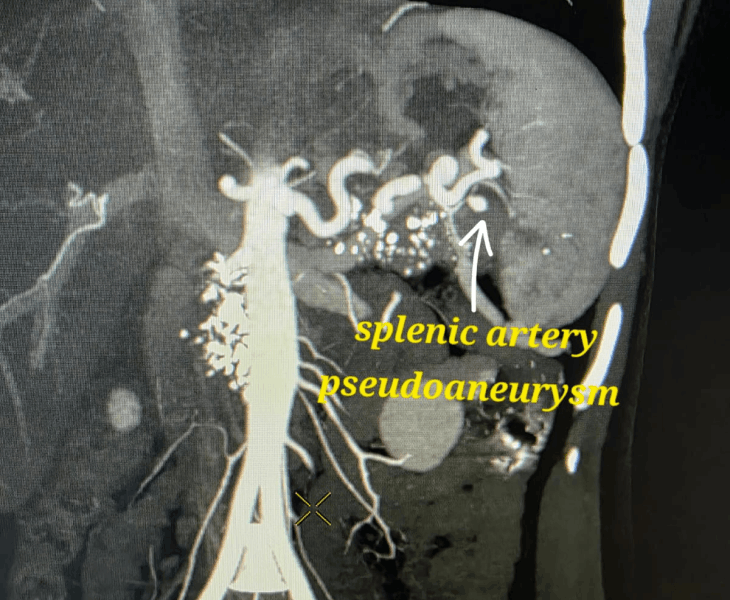

A pseudoaneurysm is a contained arterial bleed where blood escapes the artery through a tear and forms a sac outside the vessel wall. Unlike a true aneurysm, the sac is not made of normal artery wall, so it can rupture and cause severe internal bleeding.

Pseudoaneurysms can occur after trauma, surgery, procedures, pancreatitis or infection. Because they can rupture unpredictably, early diagnosis and prompt embolization is often the safest way to control bleeding.

We use CT angiography and catheter angiography to identify the bleeding vessel precisely and then perform targeted embolization to seal it while preserving as much normal organ blood supply as possible.

- Catheter angiography: contrast is injected to locate the pseudoaneurysm and bleeding source.